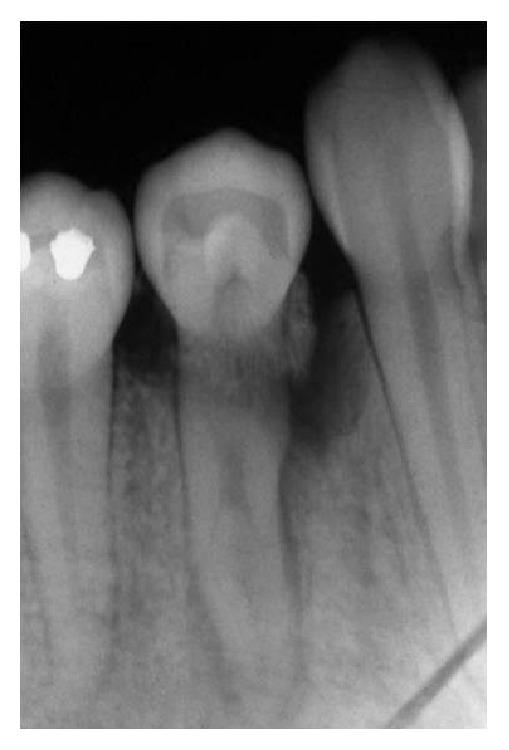

Dental anatomy is quite complex and diverse factors must be taken into account in its analysis. Teeth with anatomical variations present an increase in the rate of severity periodontal tissue destruction and therefore a higher risk of developing periodontal disease. In this context, this paper reviews the literature regarding enamel pearls and their implications in the development of severe localized periodontal disease as well as in the prognosis of periodontal therapy. Radiographic examination of a patient complaining of pain in the right side of the mandible revealed the presence of a radiopaque structure around the cervical region of lower right first premolar. Periodontal examination revealed extensive bone loss since probing depths ranged from 7.0 mm to 9.0 mm and additionally intense bleeding and suppuration. Surgical exploration detected the presence of an enamel pearl, which was removed. Assessment of the remaining supporting tissues led to the extraction of tooth 44. Local factors such as enamel pearls can lead to inadequate removal of the subgingival biofilm, thus favoring the establishment and progression of periodontal diseases.

牙齿解剖结构相当复杂,在分析时必须考虑多种不同因素。存在解剖变异的牙齿会使牙周组织破坏的严重程度增加,因此患牙周病的风险更高。在此背景下,本文回顾了有关釉珠及其在严重局限性牙周病发展以及牙周治疗预后方面影响的文献。对一名主诉下颌右侧疼痛的患者进行的影像学检查显示,右下第一前磨牙颈部区域周围存在一个不透射线的结构。牙周检查发现广泛的骨质流失,因为探诊深度在7.0毫米至9.0毫米之间,此外还有严重出血和化脓。手术探查发现存在一颗釉珠,并将其取出。对剩余支持组织的评估导致拔除了44号牙。诸如釉珠等局部因素会导致龈下生物膜清除不充分,从而有利于牙周病的形成和进展。